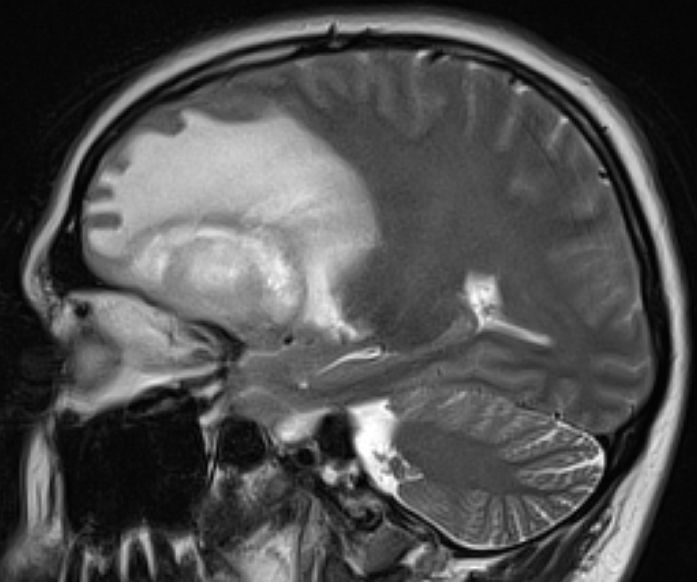

Glioblastom als Rezidiv eines Astrozytoms |

36-jähriger Mann, der vor 7 Jahres ein rechts-frontales Astrozytom Grad II mit Übergang in ein anaplastisches Astrozytom III hatte.![]() |

Jetzt Krampfanfall. Das MRT zeigt ein großes frontales Schmetterlingsgliom.![]() | |||

Die MRT-Kontrolle mit KM vor einem Jahr zeigt eine unauffällige Resektionshöhle.![]() |